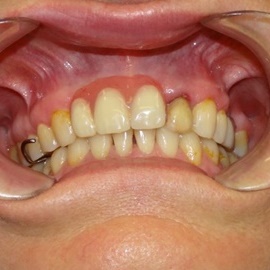

Pacjentka lat 58, prowadzi aktywne życie zawodowe. Odczuwała dyskomfort przy użytkowaniu protezy, dodatkowo przy uśmiechu odsłaniała klamry utrzymujące protezę.

Pacjentka lat 68, prowadzi aktywny tryb życia, dużo podróżuje, przeszkadzały jej klamry widoczne na zębach przy uśmiechu, oraz słaba stabilność protezy, co powodowało dyskomfort przy użytkowaniu.

Pacjentka prowadzi aktywne życie zawodowe, niedawno zakończyła leczenie ortodontyczne, niestety nie nastąpiło po nim właściwe leczenie protetyczne. Użytkowała protezę ruchomą z klamrami dziąsłowymi.

Hybrydowe podparcie protezy ruchomej na jednym implancie i jednym własnym zębie. Nie zawsze możemy osadzić u pacjenta dwa implanty. Przykłady hybrydowego podparcia protezy ruchomej na atachmentach opartych na własnym zębie i implancie.